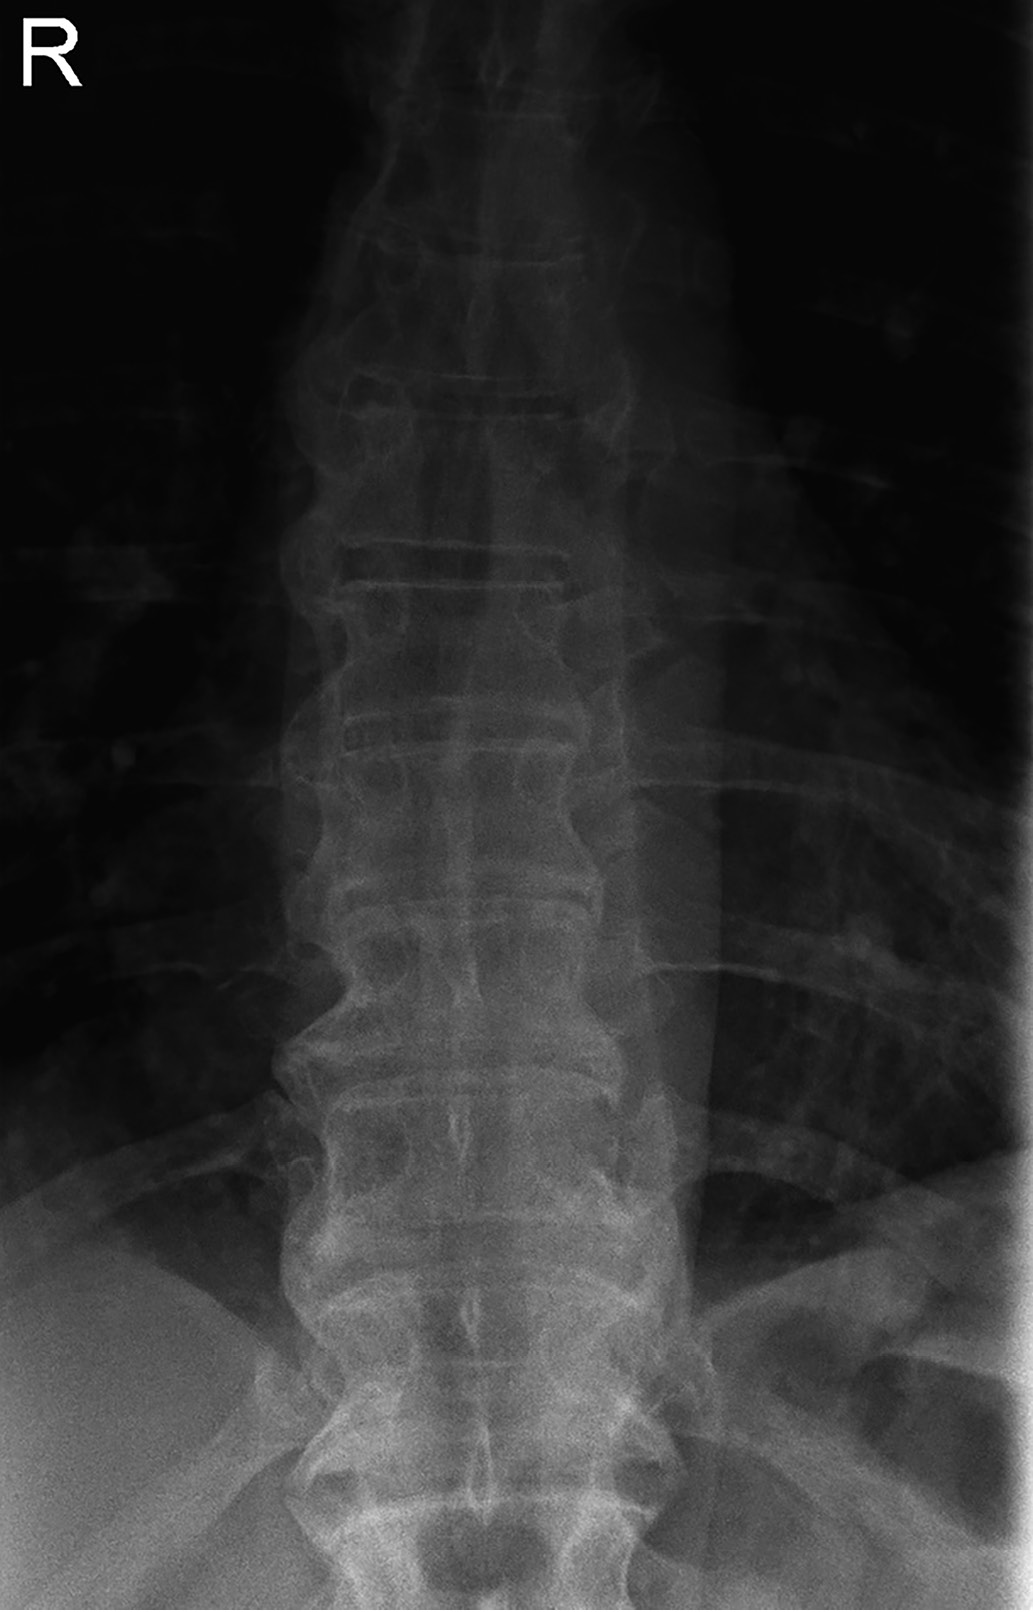

3. Fig. 3. Pronounced calcification of the anterior longitudinal ligament of the thoracic and lumbar spine, mainly on the right in a patient born in 1960 with acromegaly. | |